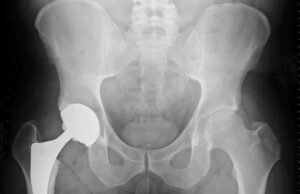

طلب الطبيب إجراء أشعة رنين مغناطيسي على مفصل الفخذ، فجاءت النتيجة صادمة، لكنها متوقعة من الناحية الطبية:

- تآكُل في مفصل الفخذ

- ضعف في وصول الدم لرأس عظمة الفخذ

- تغيرات تشير إلى «نخر عظمي» نتيجة تأثير الكورتيزون على الدورة الدموية المغذية للمفصل

هذا النمط من التلف يحدث عندما يتأثر تدفق الدم إلى العظام، ما يؤدي إلى موت جزء من النسيج العظمي تدريجيًّا، ومع الوقت يتآكل المفصل ويصبح مؤلمًا وغير قادر على أداء وظيفته.

أُصيبت أسرة الشابة وزوجها بصدمة كبيرة عندما علموا أن الحل الجراحي هو:

- تغيير مفصل الفخذ بمفصل صناعي في عمر لا يزال في بدايات الشباب